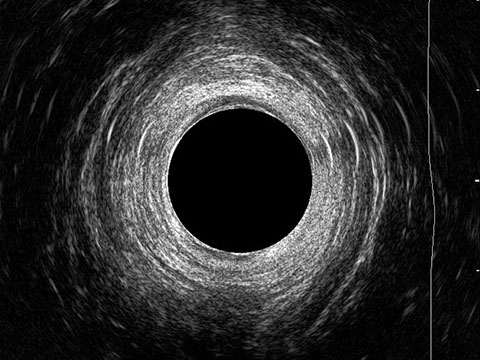

L’ecografia transanale è un esame diagnostico per immagini che consiste nell’introduzione di un trasduttore ad ultrasuoni. Le immagini qualitativamente migliori del canale anale sono ottenute usando un trasduttore rotante, montato in un manipolo rigido, che fornisce un’immagine a 360°. Con le apparecchiature più moderne è anche possibile ottenere immagini tridimensionali.

L’ecografia transanale permette di distinguere la sottomucosa che riveste il canale anale, lo sfintere anale interno, e lo sfintere anale esterno.

Le principali indicazioni all’esecuzione di tale esame sono lo studio dell’integrità delle strutture muscolari nei casi di incontinenza fecale, lo studio topografico dei processi settici perianali (ascessi e fistole) e lo studio dei processi proliferativi epiteliali (carcinoma anale).

Proctal dispone di apparecchiatura per ecografia endoanale 3D con sonda rotante.